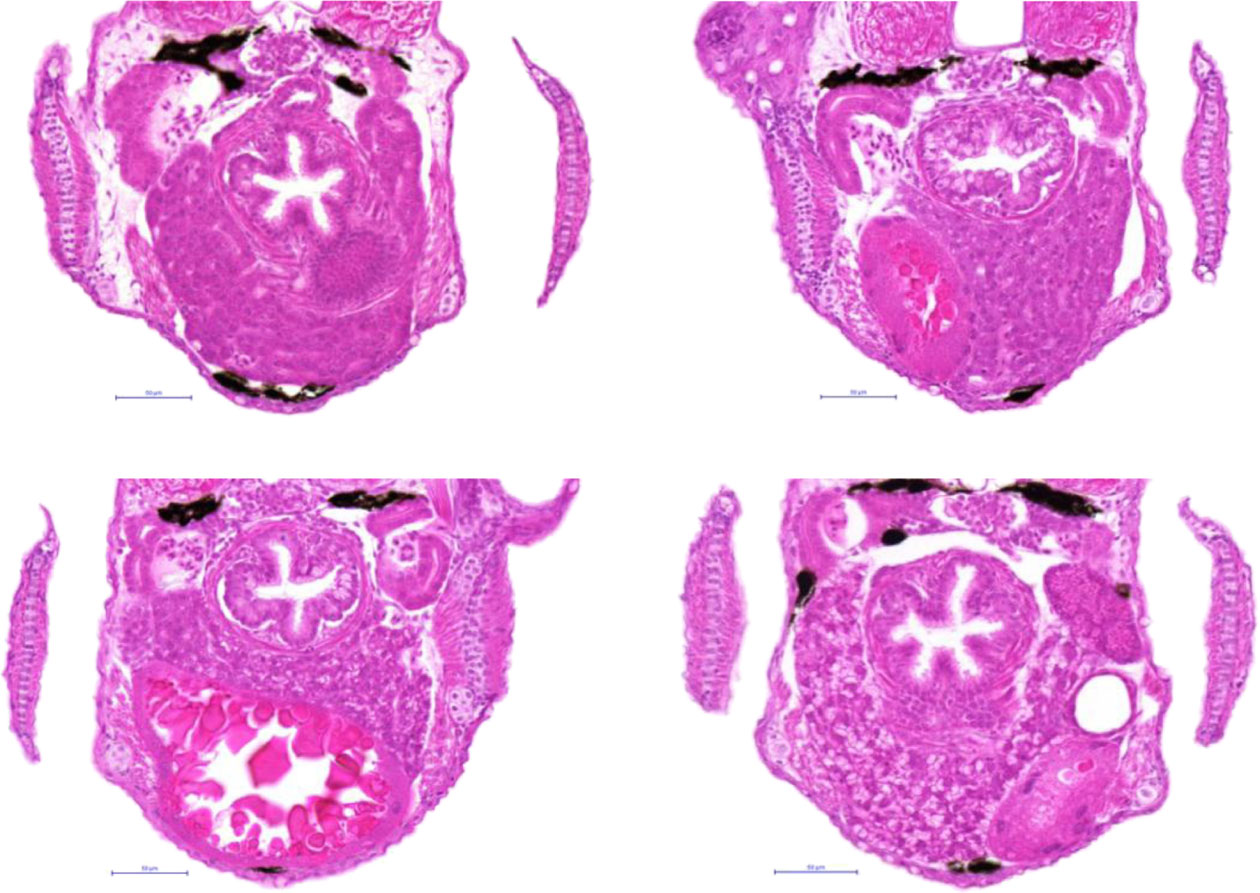

Fig. 3

Hepatocellular glycogen variation in control livers. Histopathological analysis of transversal HE sections of control larvae showing varying levels of glycogen accumulation from no observable accumulation (A), to minimal (B), very mild (C) and mild accumulation (D). Yellow border indicates the liver. Magnification 400×.